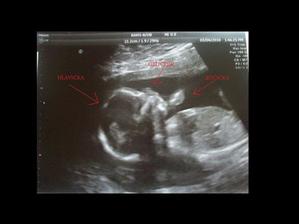

4.3.2010 byla jsem na UTZ v Praze, jestli je všechno v pořádku, tak to vypadá, že je a paní doktorka hledala pindíka a nenašla ho, tak to vypadá na holčičku 🙂 jsme moc rádi, snad to vyjde 🙂